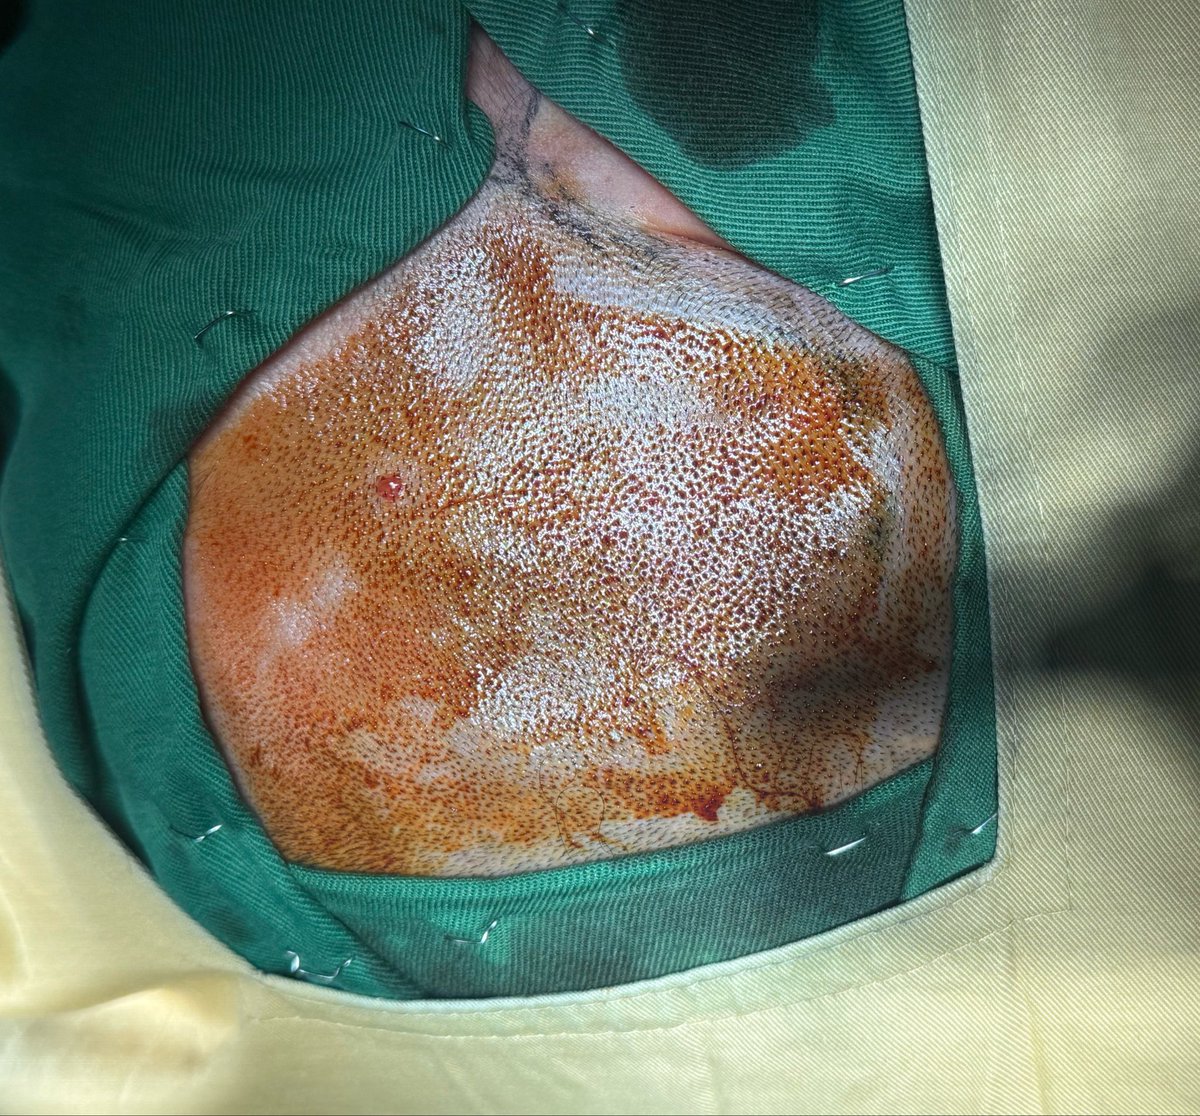

@Afgneurosurgeon Excellent low convexity temporal meningioma resection histopathological confirmation of WHO grade I?

KK Zadran@Afgneurosurgeon·

Temporal Lobe meningioma Low convexity operated